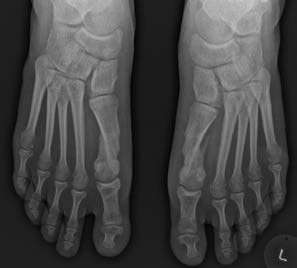

Seule la chirurgie permet de corriger, le plus souvent définitivement, la position de l’orteil. L’importance des corrections à effectuer se calcule sur base d’un bilan radiographique en charge. L’intervention est le plus souvent réalisée sous anesthésie générale couplée à un bloc locorégional. Elle peut aussi être réalisée sous rachianesthésie ou parfois sous bloc seul chez un patient bien sélectionné. En cas de déformation bilatérale, les deux côtés peuvent être opérés en même temps si le patient le souhaite.

Radiographie pré-opératoire en charge d’un hallux valgus bilatéral